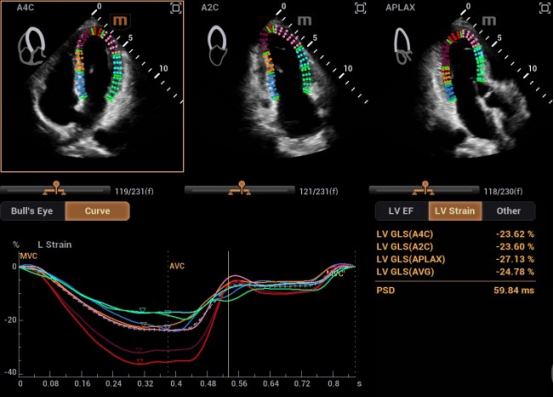

在研发中,迈瑞研发团队另辟蹊径,推出了自动左心室应变评估 Auto Strain LV 。该功能不再依赖心电信号作为“时间坐标”,而是让AI直接识别心脏机械运动的关键节点——当二尖瓣关闭、主动脉瓣开放,这些瓣膜运动的瞬间,就是心脏收缩与舒张的自然锚点。

自动左心室应变评估 Auto Strain LV(非心电触发)

迈瑞也在与尹立雪教授团队牵头的合作项目中,挖掘出自动左心室应变评估 Auto Strain LV 更多的临床应用价值,成功让心肌应变检测技术摆脱“心电图(ECG)”的束缚。尹教授表示:“基于人工智能的图像技术,现在已实现无需同步心电图的自动心肌应变分析。该技术操作便捷,检测结果与传统方法高度一致,且能早于传统指标识别心肌功能异常,为疾病早期干预提供关键支撑。”

摆脱心电图束缚后的心肌应变测量技术最明显的变化就是“快”。应用新技术后,临床检查的操作时间从10分钟缩短至3分钟以内,显著地降低了技术门槛,让床旁、急诊、大规模筛查成为可能。

同时,这项技术的数据直接源于机械运动的时相判定,没有电信号干扰与延迟误差,更真实地反映心脏“做了什么”。有效避免了心律失常、起搏器植入、幼儿及急诊术中等场景下,心电信号出现缺失、干扰的影响。

以房颤患者为例——这类人群心衰风险高,但传统心肌应变因心率变异超过10%而无法准确评估,医生只能依赖目测或射血分数等“宏观指标”,错过早期干预时机。应用非心电触发技术后,临床医生能够对房颤患者的心肌功能进行量化评估,为抗心衰治疗提供客观依据。